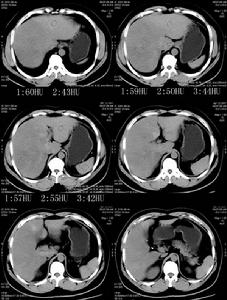

其它輔助檢查影像學檢查心電圖檢查和B超檢查等,有相應發現,可助診斷與鑑別診斷。